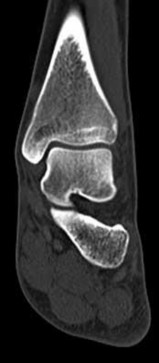

Question 10:

A 30-year-old female sustains a midfoot injury after falling from a horse. Radiographs demonstrate diastasis between the bases of the 1st and 2nd metatarsals. In a normal anatomic state, the native Lisfranc ligament originates and inserts on which two bony structures?

Correct Answer: Lateral aspect of the medial cuneiform to the medial aspect of the base of the 2nd metatarsal

Explanation:

The Lisfranc ligament is a stout, obliquely oriented intra-articular ligament that acts as the primary stabilizer of the second tarsometatarsal joint complex. It connects the lateral aspect of the medial cuneiform to the medial aspect of the base of the second metatarsal. Importantly, there is no direct ligamentous connection between the bases of the first and second metatarsals.